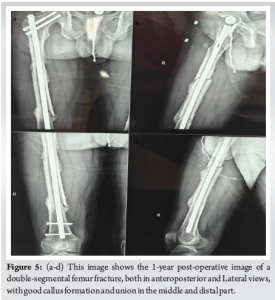

Since Hb was 8.1 g/dL and HCT was 24.5%, the patient received an additional unit of packed RBCs on the 1st post-operative day and X-ray was done as shown in (Fig. 3). On the 2nd post-operative day, in-bed turning, active quadriceps, hamstrings, and ankle pump was initiated, and on the 5th post-operative day, he was allowed to touch down while bearing weight. Using a walker, partial weight-bearing was started on the 10th post-operative day. After being admitted to the hospital for 11 days, the patient was released. During his hospital stay, no other issues were observed. He was told to attend physiotherapy sessions after being released from the hospital, and several routine follow-up appointments were planned. Bone union was assessed using both radiological and clinical parameters throughout the follow-up period, after 3 months (Fig. 4) shows good callus formation. The knee range of motion after 90 days was adequate (full knee extension and up to 115° of flexion), and callus formation was noted at the 3-month follow-up visit. Ultimately, 120 days after surgery, he was able to bear his entire weight without help. The patient cautiously resumed his pre-fracture activities after radiological evaluations at the 6- and 9-month follow-up visits showed satisfactory fracture healing. During the 12-month follow-up period, the patient was completely content with the functionality of his limbs and was able to go about his everyday activities without experiencing any problems (Fig. 5 and 6).